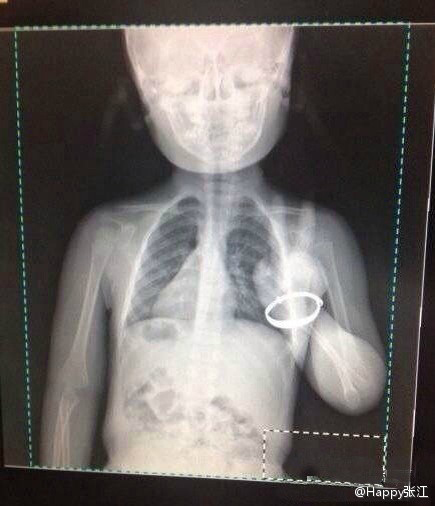

![]() @林中侠行:2014宁海越野挑战赛在大雨中开幕,这是微友从东海云顶传回的实时画面,这位参赛者从杜鹃山妙相寺到东海云顶38公里登山步道只用时3个半小时,太牛了! ![]() @明子Mia:9月21日大雨,宁海越野赛,明子同学成功完赛,44.5公里,六小时五十几分钟,第一次踩到牛粪,第一次在雨中边吃面包边跑……各种虐各种开心,可惜,没有50公里。 ![]() @不空:朋友请喝盐渍樱花茶,是她在春天樱花开放时采来的花朵,用盐、梅汁加以腌渍,并冷藏保存。这样一杯茶,有着春花淡淡的香气,还有梅子若有若无的甘甜。泡开时,那些尘封了一个夏季的花朵便轻盈地绽放在杯中。这样一杯茶,喝的是春天,是秋天,更是美好的心情。 ![]() @Happy张江:论坛里看到一位放射科医生的亲身经历,笑cry!一天两夫妻带个小女孩来拍胸片。小孩各种哭,声嘶力竭。这事医生有经验啊,上去哄,小美女,叔叔这是照相的,不疼,一哭照出来就不漂亮了,小孩一听立马不哭了,医生赶紧回操作间曝光。图像出来以后,尼玛,熊孩子你过来,保证不打死你……经典剪刀手。 |